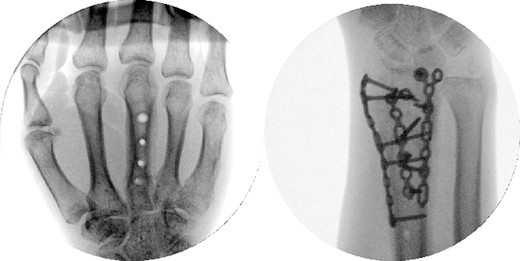

Two weeks following the procedure, the patient returned to the clinic for a follow-up visit. The wrist was swollen and ROM was limited. Hand motor functions and neurovascular exam were fully intact. Radiographs taken in clinic showed intact hardware with healing fracture. At 2 months follow-up, radiographs showed intact hardware with interval bone bridging across fracture sites. Radiographic parameters including articular alignment, radial height, radial inclination, and volar tilt were in acceptable ranges (Fig. 5). The patient reported no concerns or complications. A computed tomography (CT) scan was obtained at 10 weeks after the procedure and confirmed adequate bony healing and alignment without failure (Fig. 6). The dorsal spanning plate was eventually removed 1 month later and 4 months since the initial operation (Fig. 7).

CT assessment at 10 weeks postprocedure with coronal and sagittal cuts.